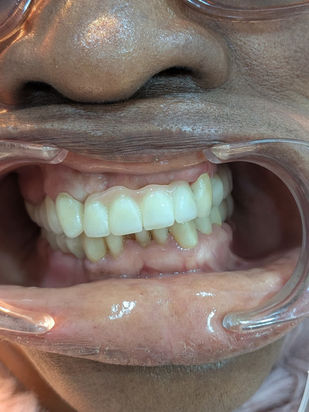

Une preuve de notre expertise : Voici un exemple concret d'une restauration complète réalisée récemment. Ce patient a reçu 11 implants dentaires au total, retrouvant une dentition parfaite et fonctionnelle à un prix incroyable, bien inférieur aux tarifs pratiqués en Europe ou en Amérique.